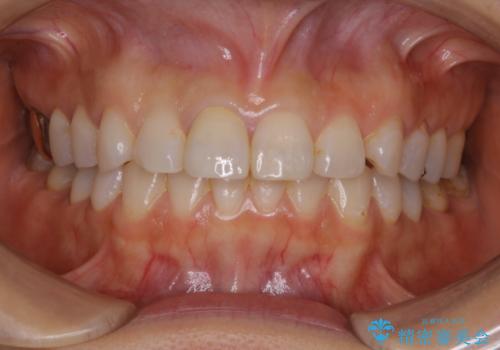

何度も欠けてしまう前歯を被せ物で治療

- プラスチックで治療している前歯が何度も欠けてしまうとお悩みで来院された方です。

歯全体を覆うクラウンにて治療を行いました。

前歯1本のみの被せ物治療を行う場合、他の歯を参考に歯の色や形を忠実に再現することが重要です。オールセラミッククラウン(スペシャル・エクセレント)は、事前に歯科技工士との打ち合わせを行うことで、歯の色や形、さらには患者様のご希望も聴取したうえでクラウンを作製することが可能です。